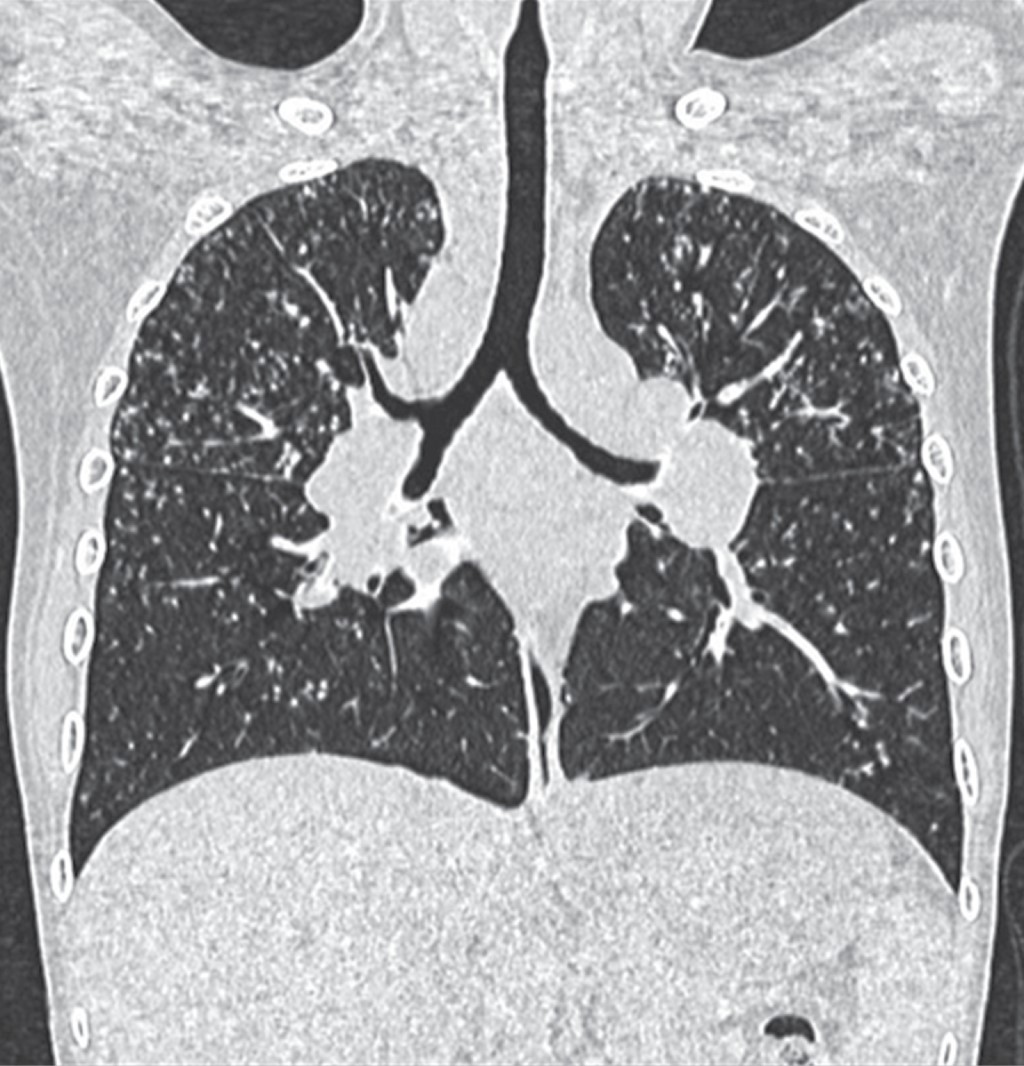

Ante este deterioro acude nuevamente a nuestro servicio y recibe tratamiento con prednisona a 1 mg/kg/día y metotrexato a 15 mg/m2/semana y se suspende micofenolato de mofetilo; con este cambio, a los dos meses de tratamiento hubo mejoría de la uveítis, sin depósitos, ni queratopatía y presión intraocular normal, la sintomatología respiratoria desapareció y hubo evidente mejoría por radiografía de tórax y por TACAR con desaparición de los crecimientos ganglionares parahiliares, de las imágenes micronodulares y del patrón intersticial (Figura 7).

Las pruebas de función respiratoria iniciales mostraron un patrón sugestivo de restricción moderada, sin respuesta significativa al broncodilatador. La broncoscopia mostró traqueobronquitis leve y gastritis antral, baciloscopias en serie de tres y prueba de PPD reportadas negativas. La biopsia de piel reveló granulomas desnudos compatibles con sarcoidosis. Para la uveítis recibió prednisona ocular al 1%. Fue tratado por otro servicio con tres pulsos de metilprednisolona a 30 mg/kg/día, prednisona oral a 0.7 mg/kg/día y micofenolato de mofetilo 42 mg/kg/día (1 g VO cada 12 horas) sin respuesta. Cambiamos a prednisona en dosis de 1 mg/kg/día y metotrexato a 15 mg/m2/semana, hubo respuesta favorable desde las cuatro primeras semanas de tratamiento; la enfermedad está inactiva, pero el paciente cursa con tos, disnea, cianosis distal, y baja saturación de O2, todo lo anterior traduce un daño pulmonar permanente (Figuras 13 y 14).

Figura 7

Figura 13

Figura 14